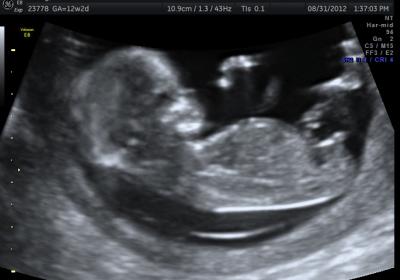

this was a surprise pregnancy 2 weeks after starting my low everything. i am pretty sure it will be a boy, which is ok, but any chance it is a girl? I think age is closer to 12w 5 days

Hi and congrats on your pregnancy! I also officially started my sway 2 weeks before I fell pregnant. So I think it can go either way. Spine isn't flat so it's hard to tell. I don't think the angle is high "enough" for me to official give a boy guess. My dd's nub at that same gestation tilted up a bit and got many mixed reviews. I would say I got more boy guesses than girl and most 50/50.

I think it looks like boy nubs

The bulb on the end makes it appear more boy than girl but my sons was much more angled than that.

Thats a tough one, I would lean boy slightly because of the shape x

I think boy

i thought the angle looked kind of girlish but the shape looked boy to me...i guess angle is not everything.

Id say boy, but you never know.

I'm guessing boy too x